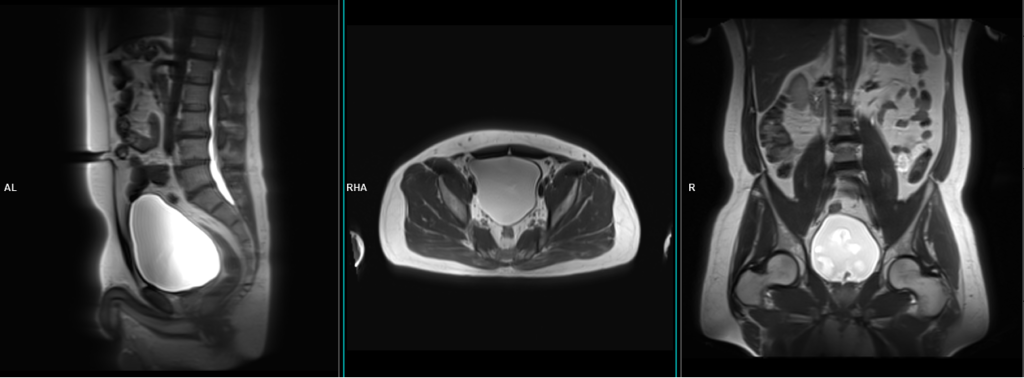

A three-plane T2-weighted HASTE localizer must be taken initially to localize and plan the sequences. These fast, single-shot localizers usually have an acquisition time of less than 25 seconds, which is excellent for localizing pelvic structures.

T2 tse sagittal 3mm SFOV

Plan the sagittal slices on the coronal plane, angling the positioning block parallel to the urinary bladder (i.e., parallel to the pubic symphysis and median sacral crest). Check the positioning block in the other two planes. An appropriate angle must be given in the axial plane (parallel to the line along the linea alba and the median sacral crest). Slices should be sufficient to cover the entire urinary bladder from the right acetabular rim to the left acetabular rim. Using a saturation band above and in front of the sagittal block will help reduce artifacts caused by breathing and peristalsis.

TR 4000-5000 | TE 100-120 | SLICE 3 MM | FLIP 130-150 | PHASE A>P | MATRIX 320X320 | FOV 200-250 | GAP 10% | NEX(AVRAGE) 2 |

T2 tse axial 3mm SFOV

Plan the axial slices on the sagittal plane and angle the positioning block horizontally across the urinary bladder. Check the positioning block in the other two planes. An appropriate angle must be given in the coronal plane, horizontally across the urinary bladder. Slices should be sufficient to cover the urinary bladder from L1 down to two slices below the symphysis pubis. To reduce artifacts from breathing and peristalsis, consider using a saturation band above and in front of the axial block.

TR 4000-6000 | TE 100-120 | SLICE 3 MM | FLIP 130-150 | PHASE R>L | MATRIX 320X320 | FOV 200-250 | GAP 10% | NEX(AVRAGE) 2 |

T2 tse coronal 3mm SFOV

Plan the coronal slices on the sagittal plane; angle the positioning block vertically through the urinary bladder. Check the positioning block in the other two planes. An appropriate angle must be given in the axial plane (parallel to the right and left hip joints). Slices must be sufficient to cover the entire urinary bladder from the anterior abdominal wall up to the rectum. Using a saturation band above and in front of the coronal block will help reduce artifacts from breathing and peristalsis.

TR 4000-5000 | TE 100-120 | SLICE 3 MM | FLIP 130-150 | PHASE R>L | MATRIX 320X256 | FOV 200-250 | GAP 10% | NEX(AVRAGE) 2 |